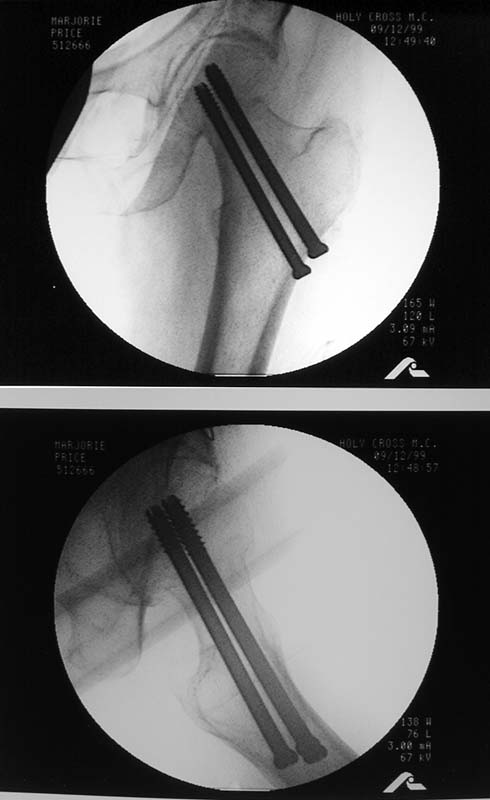

Does anyone on the list know of any references regarding the placement of cannulated hip screws above/below the lesser trochanter as it relates to the risk of subsequent subtroch fracture? i know placement should be above the lesser trochanter but i have been unable to find evidence to support this. thank you.

Reported 20% incidence of fracture if screws are placed too low, below the lesser trochanter, or  with un-filled drill holes there too. I have not looked at it in a long time but I believe the reference on this topic is: Karr, Clin Ortho Rel Res 1985.